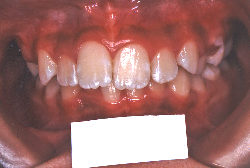

「前歯が重ならない」という主訴で来院したケースです。診断の結果、「重症の開咬」と判明しました。

この方の場合は、マルチブラケット装置は、歯の位置づけを3次元的に正確に行うことの出来る最善の矯正方法です。したがって開咬の治療も、形の改善としては問題なく行うことが出来ます。しかし、開咬が他の症状と少し違う点は、舌や唇の動かし方に問題があることから生じた症状なので、この問題を放置したまま形だけを作っても、時間が経つと簡単に後戻りしてしまうという問題です。つまり、マルチブラケット法で形態の矯正をするのと同時に、原因となっている筋肉の動きを正常に修正しなければなりません。この筋肉の動きを正常に修正する治療が、"筋機能訓練療法(Myo-functional therapy:略してMFT)"といわれるものです。

筋機能訓練療法は、筋機能訓練療法士という特別なトレーニングを積んだ歯科衛生士が行います。内容的には、いろいろなメニューがあり、簡単なものから始めて少しずつ筋肉の力を強めていき最終的には、無意識に起きる舌の突出をなくし、正しい摂食嚥下運動を獲得するまでトレーニングしていきます。この症例は、もちろん筋機能訓練にもしっかり取り組みました。治療後は開咬が改善しただけでなく、出っ歯の症状もなくなり唇の審美性が大幅に改善しました。もちろん奥歯の噛み合わせも正しい状態が確立しています。